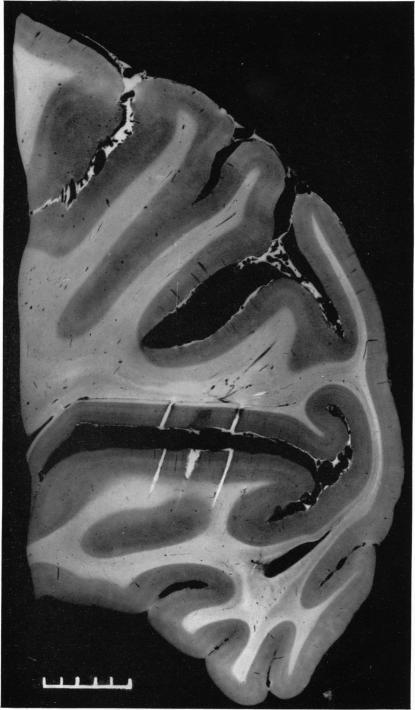

The representation of the visual field on the cerebral cortex in monkeys.

J Physiol. 1961 Dec;159(2):203-21. doi: 10.1113/jphysiol.1961.sp006803.